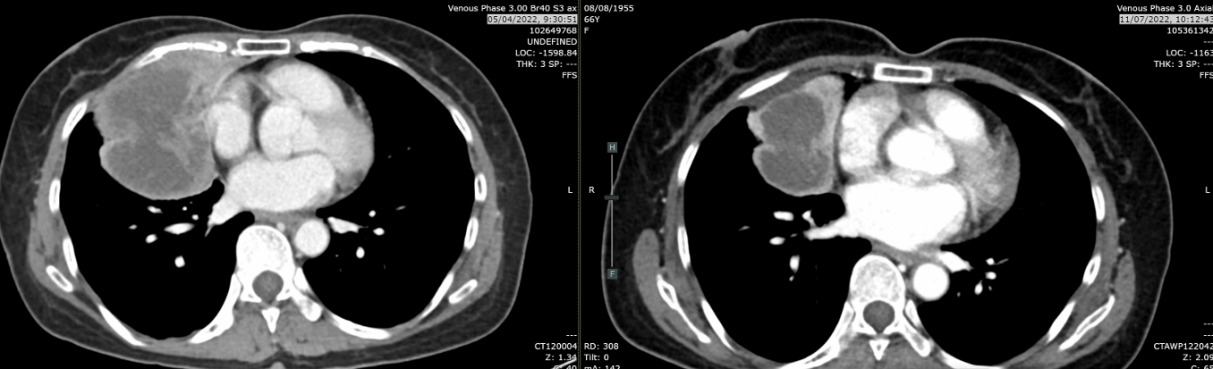

胸部增强CT(2021-12-21):右肺中叶及右肺下叶前基底段巨大软组织密度肿块,大小约6.8×6.3×8.5cm,边界不清;右肺上叶及下叶多发磨玻璃结节(最大1.0cm),考虑肺内转移;纵隔及双侧腋窝多发淋巴结融合肿大;左侧肾上腺见0.9×0.8cm低密度结节,可疑转移。气管及主支气管通畅,无胸腔积液,无骨破坏。

复查CT(2022-03-07):肿块增大至8.9cm,伴阻塞性肺炎,多发淋巴结最大达3.4cm。

复查CT(2022-04-05):肿块进展至9.4×7.7×7.1cm,侵犯右侧叶间裂、膈肌、胸壁及心包(脂肪间隙消失)。右肺多发纯磨玻璃结节0.4-1.0cm,考虑原位腺癌或非典型腺瘤样增生。纵隔淋巴结分布于右肺门、隆突下、右上及下气管旁区域,以及左上气管旁区域,最大3.3cm(隆突下)。